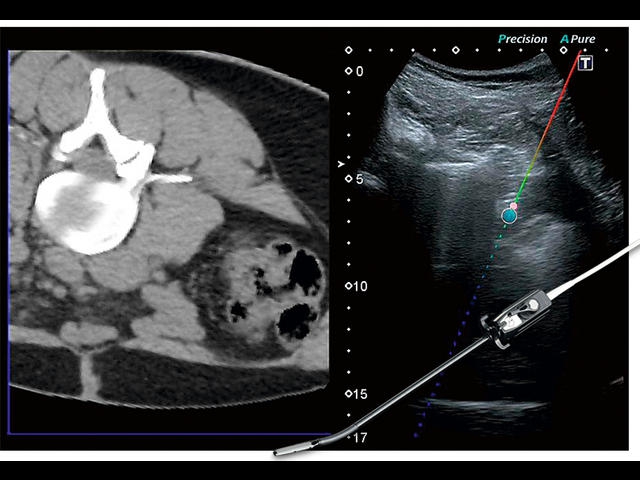

Обновленная версия легендарного УЗ-сканера. Стационарный аппарат экспертного класса Aplio 500 Toshiba NEW, визуализирует анатомические структуры в высоком разрешении. Модель позволяет выявить микрокальцификаты, новообразования, нарушения в работе сердца, сосудов и мышц. Присутствует функция виртуальной эндоскопии, 4D-сканирования, эластометрии тканей, УЗИ с контрастированием. За повышение качества изображения отвечают технологии ApliPure и Superb Microvascular Imaging. Первая задействует возможности пространственного и частотного кодирования, формирует цельный визуальный ряд с сохранением клинических маркеров. Вторая улучшает отображение микрососудистого русла, используя доплеровский эффект. Модель оснащена 21-дюймовым монитором, имеет 4 активных порта. Возможно подключение педиатрических, интраоперационных, лапароскопических и чреспищеводных датчиков.

- Fly Thru. Виртуальная эндосонография обеспечивает построение трехмерной модели полостей, протоков и сосудов в рельном времени, облегчает организацию инвазивных процедур и динамических исследований. Посредством Fly Thru можно установить шунты и стенты, проводить точные оперативные вмешательства.